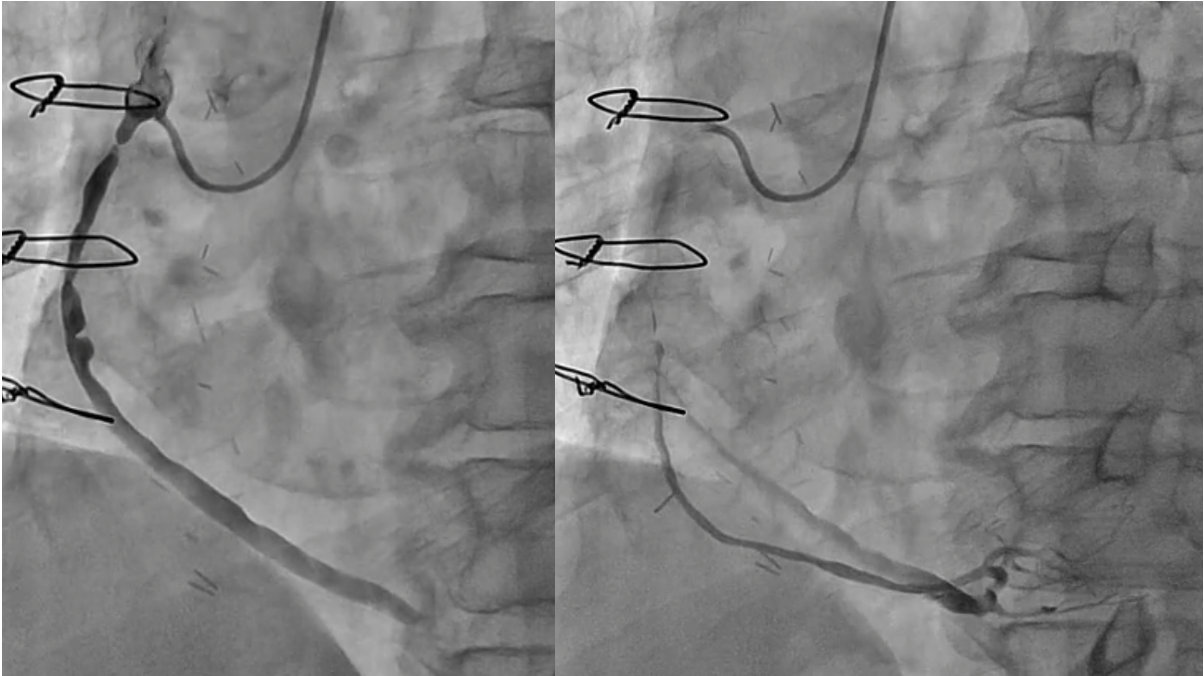

PCI for the degenerated SVG was determined to be at high risk of distal embolism so we planned to perform PCI for native RCA. Antegrade wire crossing was thought to be difficult (J-CTO score was 3 : calcification, bending and lesion length), therefore we planned retrograde approach via SVG. To avoid ischemia during the retrograde procedure, we dilated the severe stenotic lesion in SVG with small balloon and then micro catheter was advanced. It was very difficult to pass the graft anastomosis, but reverse wire technique at distal RCA was effective. Even after the advancement of both antegrade and retrograde wires, it was also difficult to pass the CTO lesion due to strong bending. Finally, retrograde wire was passed with Reverse CART technique and externalization was achieved. After DES implantation, native RCA was nicely revascularized.